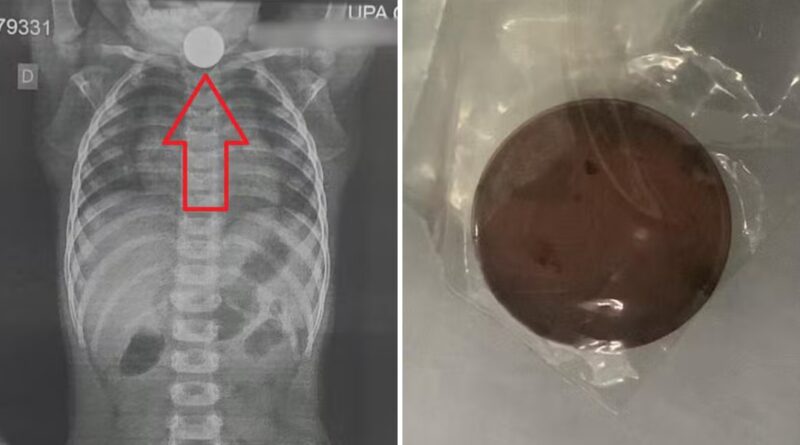

Na UPA, um raio-X revelou que a moeda estava presa no esôfago da criança, necessitando de um procedimento específico para sua remoção. A falta de recursos para realizar a endoscopia na própria cidade levou a uma transferência urgente para São Paulo, onde a bebê finalmente passou pela intervenção necessária.